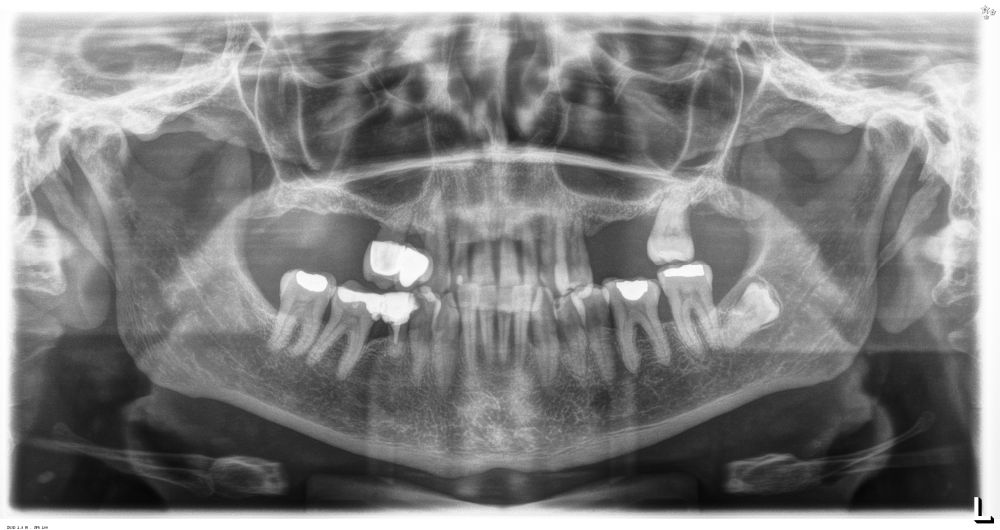

Presentamos el caso de una paciente femenina de 56 años de edad que acude a la consulta demandando un tratamiento con implantes dentales para reponer los dientes ausentes en ambos sectores posteriores maxilares. En ambos cuadrantes superiores, los molares se perdieron hace varios años. La paciente no se ha realizado la reposición de los mismos hasta ahora, ya que en otros centros consultados la propuesta terapéutica fue la de realizar injertos y regeneración ósea para poder ganar volumen óseo suficiente antes de colocar los implantes. La paciente busca otras alternativas menos invasivas y por ello acude a la visita. En las imágenes intraorales se observa la falta de los molares en los sectores posteriores maxilares con excepción del 27, que actualmente tiene un compromiso periodontal importante (Figuras 1-4). El resto de dientes también se encuentran afectados por una enfermedad periodontal avanzada con pérdida ósea horizontal (Figura 5).